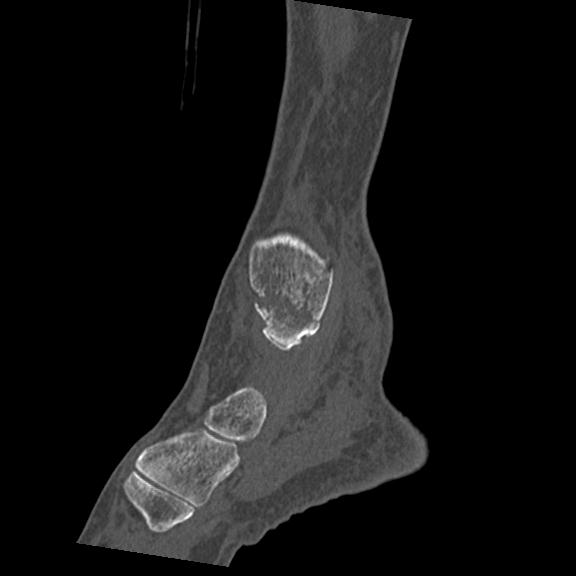

56476 8/28 4R 1/21 2R 左足関節 デジカメ写真 72歳女性 右足関節AS